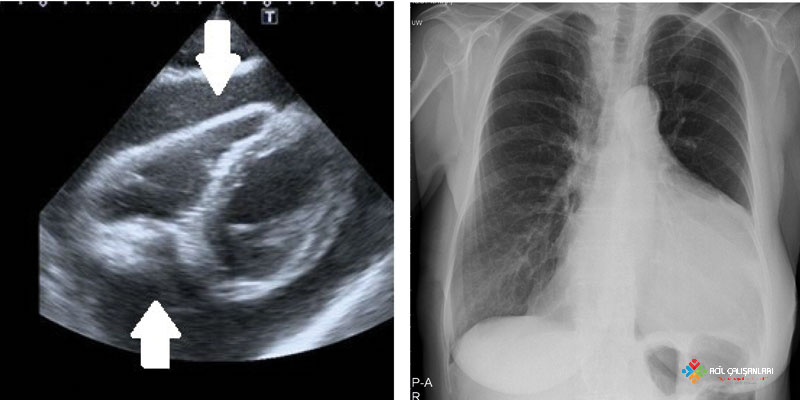

1. Ekokardiyografi (POCUS) – ALTIN STANDART

Acil serviste tanı koydurucudur. Perikard yaprakları arasında anekoik (siyah) sıvı alanı görülür.

3. Akciğer Grafisi

- Büyük effüzyonlarda kalp gölgesi genişler (Çadır Kalp / Su Matarası görünümü).

- Akut tamponadda kalp boyutu normal olabilir!